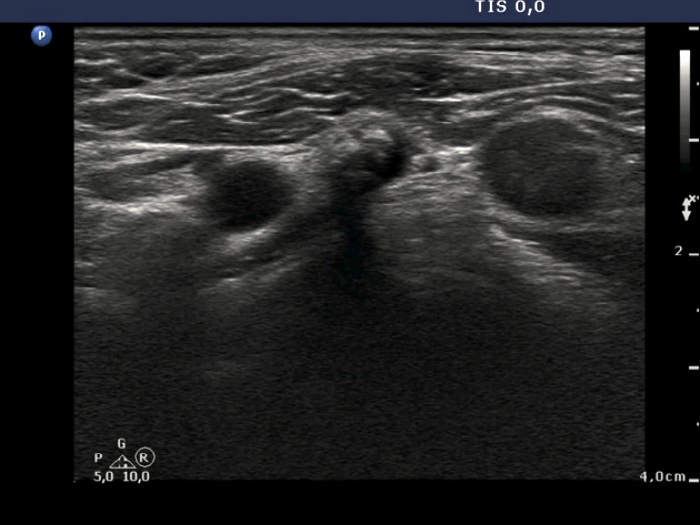

Medullary carcinoma (histological diagnosis) - case 617

Right thyroid lobe

A metastatic lymph node in the right side of the neck

There are similar hyperechogenic figures in the primary and metastatic focus. These are multiple, have an irregular shape and vary greatly in size.